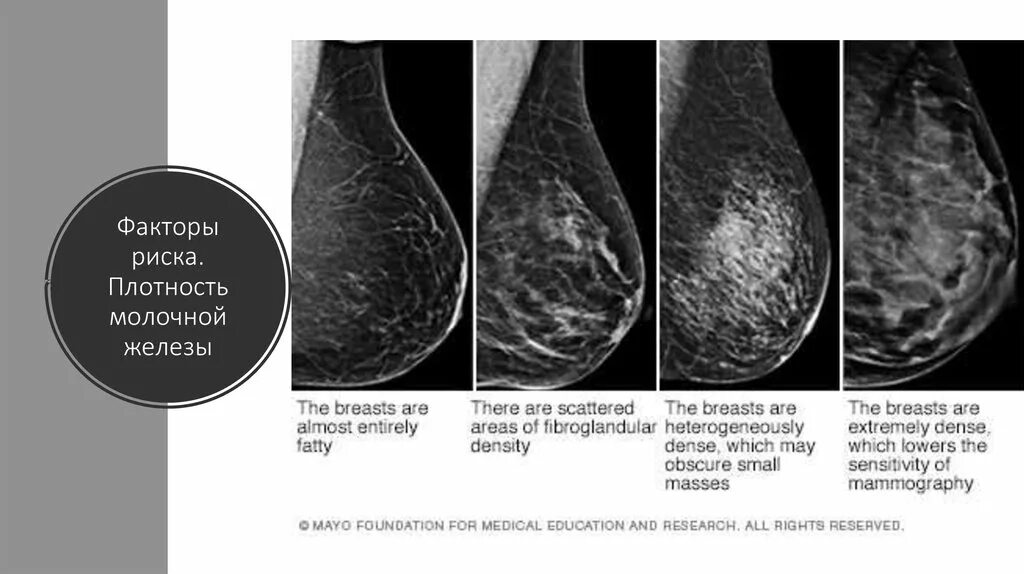

Типы молочных желез по acr